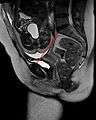

Pelvis

Conjugata vera as measured on sagittal MRI